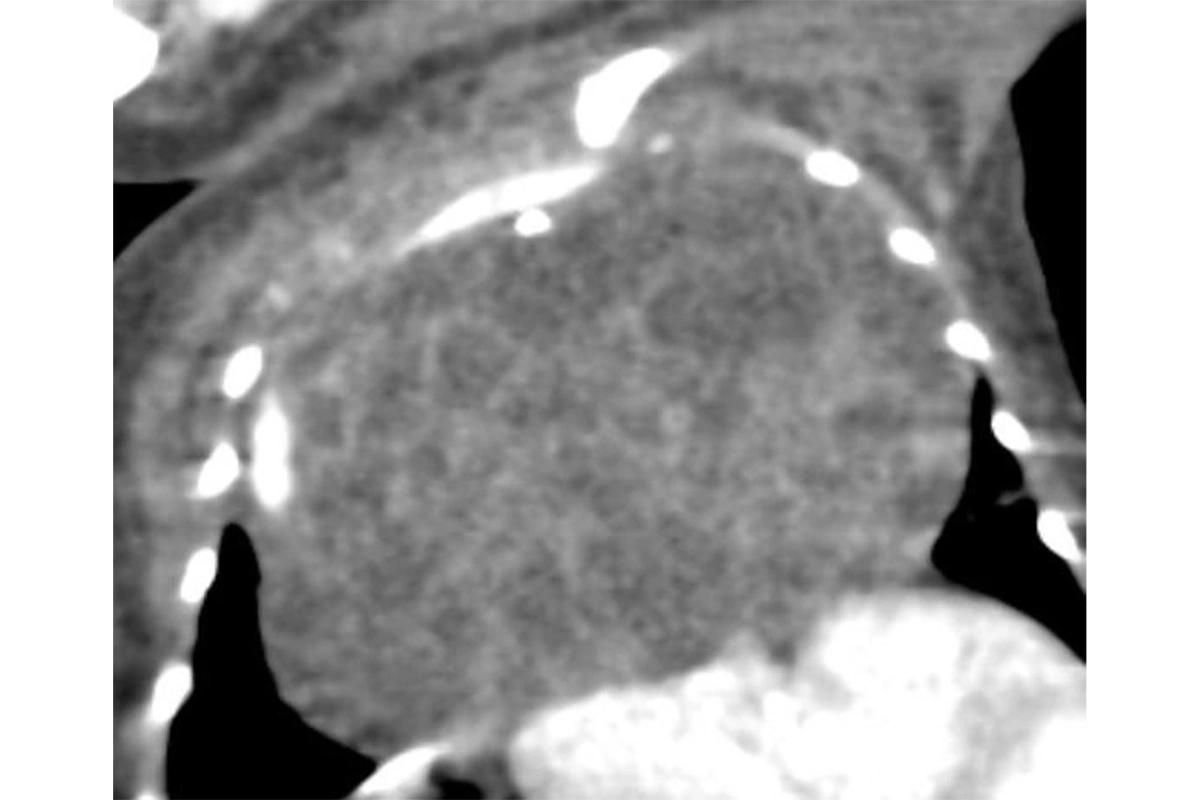

Опухоль у младенца была обнаружена еще на 30-й неделе беременности во время УЗИ, ее размер на тот момент достигал почти 8 см. Образование, по словам врачей, сдавливало легкие и сердце, угрожая его жизни. После этого вплоть до самых родов будущая мама находилась под постоянным наблюдением специалистов.

Опухоль у младенца на рентгеновском снимке

По словам врачей, единственным шансом спасти ребенка была операция по полному удалению опухоли, которая также несла определенные риски для жизни малыша. Через два часа после родов его оперативно перевели в отделение анестезиологии, реанимации и интенсивной терапии, где команда реаниматологов под руководством Натальи Геннадьевны Алейниковой боролась за стабилизацию состояния малыша в течение пяти дней. После этого хирурги Андрей Александрович Распутин и Владислав Сергеевич Черемнов с командой из шести человек успешно провели двухчасовую операцию, удалив опухоль, занимавшую всю переднюю грудную стенку.